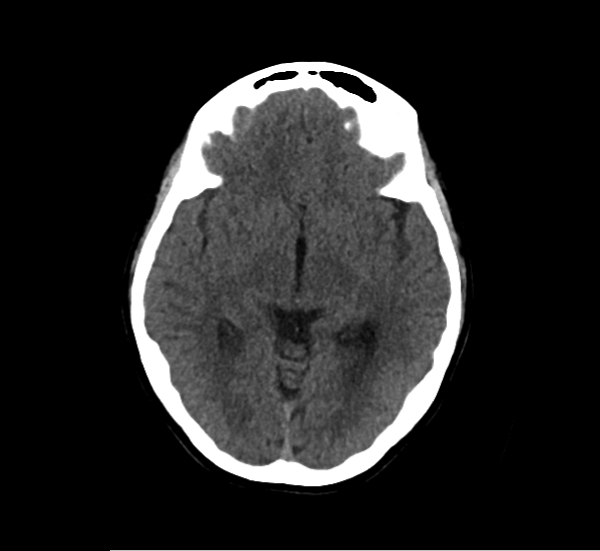

CT Brain Anatomy